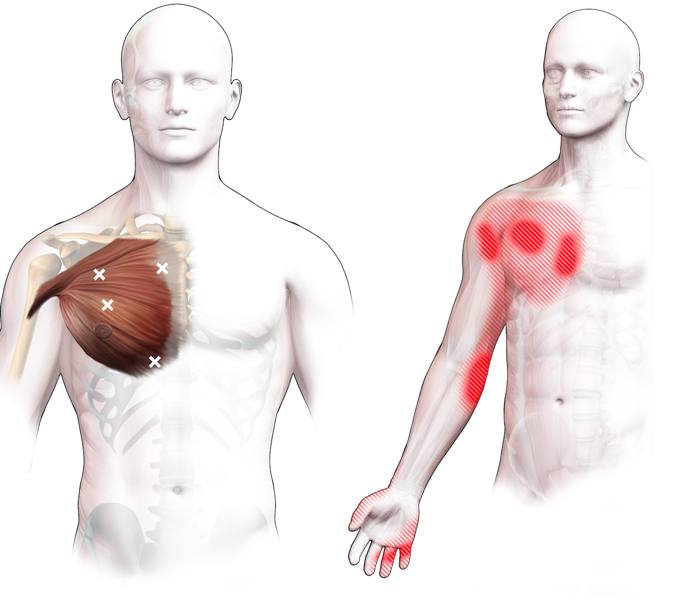

Spieren (Nederlands)

Spieren (nederlands)

Spieren (Latijn)

Spieren (latijn)